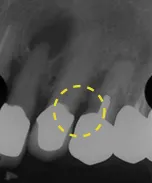

奥歯を1本長期間失ったケース

■治療前

向かって左の下の奥歯が、長期間失ったまま放置されていました。その為、向かって左奥の2本の歯が、前に倒れるように傾いてしまっていました。

まず、この傾きを治しました。治療期間は4ヶ月です。

■治療中

■治療後

■治療中レントゲン写真

その後、歯を失った場所には、人工の歯根であるインプラントを埋めて、白い歯をかぶせました。

■治療後レントゲン写真

このようにして、従来なら前と後ろの歯を削って治していくブリッジにせずに、治すことができました。

| 主訴 | 右下の奥歯をずいぶん前に抜きそのままにしていたら、奥歯が倒れてきた |

|---|---|

| 治療方法 | 部分矯正治療+インプラント治療 |

| 治療期間 | 約10か月 |

| 通院回数等 | 12回位 |

| 費用 | 約80万円 |

| リスク・副作用 | インプラント術後の腫れ・痛み |